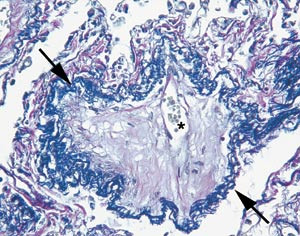

Ved innkomst ble det registrert en parasternal systolisk bilyd og en aksentuert annen hjertetone over pulmonalstedet. Elektrokardiografisk forelå det inkomplett høyre grenblokk, høyre akse og høyre ventrikkel-hypertrofi. Ekkokardiografi bekreftet funnene av hypertrofi, sammen med dilatasjon og hypokinesi av høyre ventrikkel, mens venstre ventrikkel var velfungerende. Pulmonal angiografi viste proksimalt dilaterte kar, men ingen tegn til tromboembolisme. Ved høyresidig hjertekateterisering var trykk i høyre atrium og i innkilt posisjon i a. pulmonalis normale, mens middelarterietrykk i a. pulmonalis var 44 mm Hg, minuttvolum var 2,8 l/min, lungekarmotstand var 19,5 W og metning i blandet venøst blod var 66 % (med 2 l oksygen per nesekateter). Det tilkom ingen signifikant reduksjon i trykk ved forsøk på akutt vasodilatasjon med inhalasjon av 50 g iloprost. Funksjonsundersøkelse av lungene viste redusert diffusjonskapasitet for karbonmonoksid (30 % av forventet). Røntgen thorax viste noe prominente lungekar, diskrete infiltrater og noe høyresidig pleuravæske. Ved høyresolusjons-CT av lunger var fortykkede interlobærsepta mest iøynefallende (fig 1), med mediastinale lymfeknuter og områder med mattglassforandringer og diffuse sentrilobulære mikronoduli.

Røntgen thorax vil kunne avsløre lettgradige interstitielle infiltrater eller pleuravæske av beskjeden grad. Typiske funn ved høyresolusjons-CT av lunger ved venookklusiv sykdom inkluderer mediastinal lymfadenopati, bilaterale sentrilobulære mikronoduli og fortykkede interlobære septa, med mattglassfortetninger og pleuraeffusjon (8). Sikker diagnose kan stilles ved åpen lungebiopsi, men frarådes oftest pga. pasientenes dårlige hemodynamiske status.